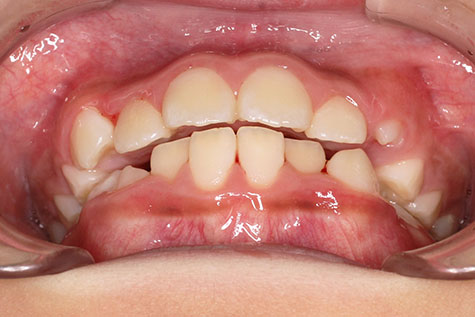

側方歯(犬歯、小臼歯)の生え変わりの時期。 前歯のがたつきを気にされ、小児矯正からの治療を希望されました。 お母様は、矯正治療経験済みですので、治療には前向きで早期治療の必要性を納得されていました。 小児矯正では、永久歯の生え変わるためのスペースを増加させ、がたつきを軽減させることを目的で行います。 残ったがたつきは、全ての永久歯が生え変わってから、本格矯正(マルチブラケット装置での治療)で改善しています。 比較的、叢生量は少ないため、本格矯正は非抜歯にて配列しました。

マルチブラケット 動的治療期間 2年6か月 調整回数16回 特に問題もなく、保定後も安定しています。